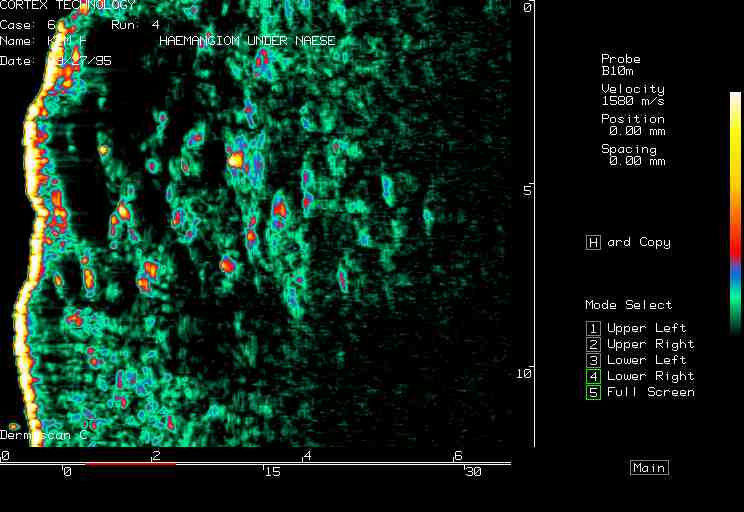

Hemangioma, nose |

Facial hemangioma 1 |

Facial hemangioma 2 |